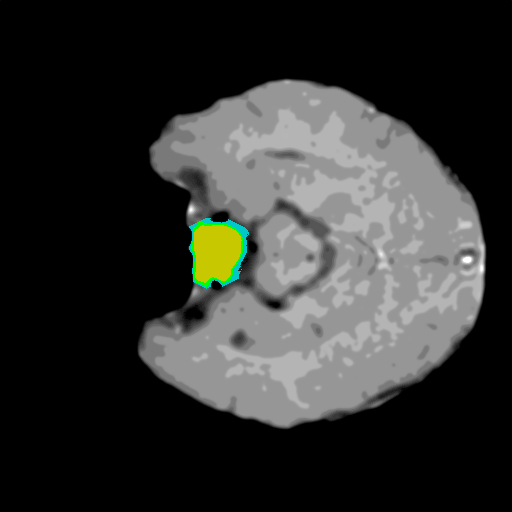

Extensive experiments have been performed in the current setup, and experimental outcomes are reported with the demonstration of numerical and statistical analyses using the proposed QFS-Net, QIS-Net [39], convolutional U-Net [18] and Residual U-Net (URes-Net) architectures [20]. The human expert segmented skull-tripped contrast enhanced DSC brain MR input image slices of size and ROIs are provided in Figure 5 as samples. The demonstration of QFS-Net segmented images followed by the essential post-processed outcome on the slice no. for class level with four distinct activation schemes () are shown in Figure 6. It is evident from the experimental data provided in Table LABEL:tab1 that the proposed QFS-Net performs optimally for the -connected quantum fuzzy pixel information heterogeneity assisted activation () with and gray scale set in comparison with other thresholding schemes and gray scale sets under the four evaluation parameters () [44]. The segmented tumors obtained using the proposed self-supervised procedure under class transition levels with four different thresholding schemes , , and are demonstrated in Figures 7- 8 for the class boundary sets and [39], respectively. The segmented images using the remaining two class boundary sets ( and ) [39] are provided in the supplementary materials section. The segmented ROIs describing the whole tumor region after the masking procedure using QIS-Net, U-Net and URes-Net are also reported in Figure 9.